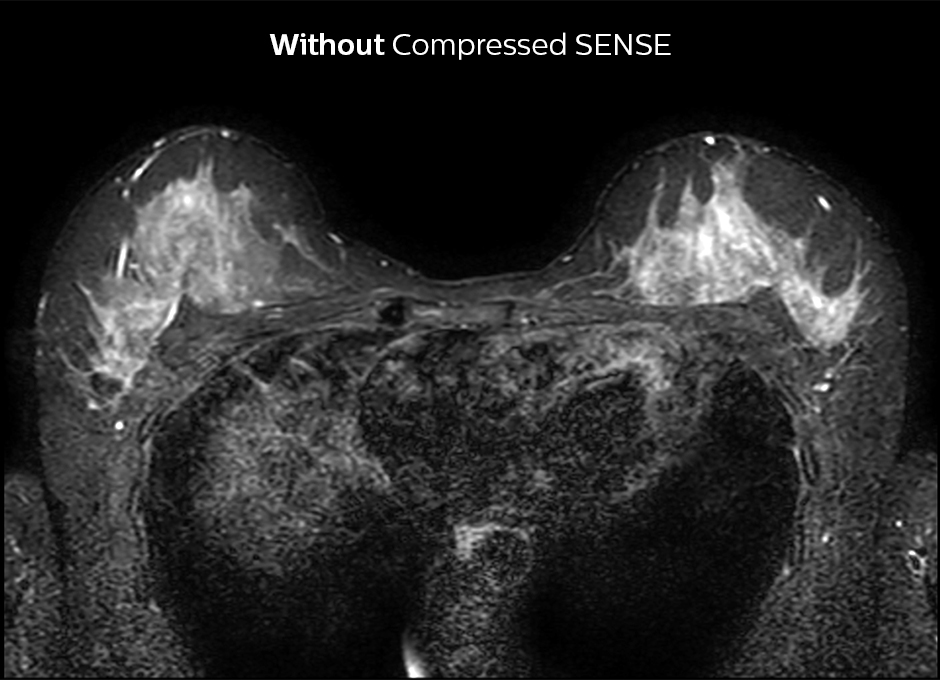

Accelerating 2D breast MRI

Compressed SENSE allows 29% shorter scan time with similar spatial resolution.

2D STIR breast WITHOUT Compressed SENSE

2D STIR, scan time 3:39 min, voxel size 1 x 1.25 x 3 mm.

2D STIR breast Compressed SENSE factor3

2D STIR, scan time 2:36 min, voxel size 1 x 1.26 x 3 mm.